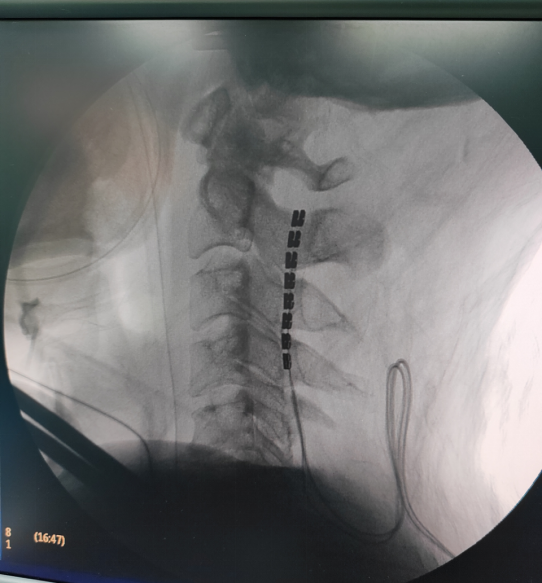

该手术无需开颅,只需要从患者颈部切开一个小口,将一个微型电极植入颈椎C2-4水平硬脊膜外即可,连接刺激器,依据患者不同阶段的评估结果,设定个体化刺激参数方案,进行促醒治疗。

脊髓处植入电极

脊髓电刺激术是通过在颈髓 C2-4水平硬膜外放置刺激电极,脉冲刺激经上行网状激活系统传至大脑皮质,增加脑的局部葡萄糖代谢率及脑血流,促进兴奋性递质的释放,增强意识冲动及脑电活动,从而达到昏迷促醒效果。